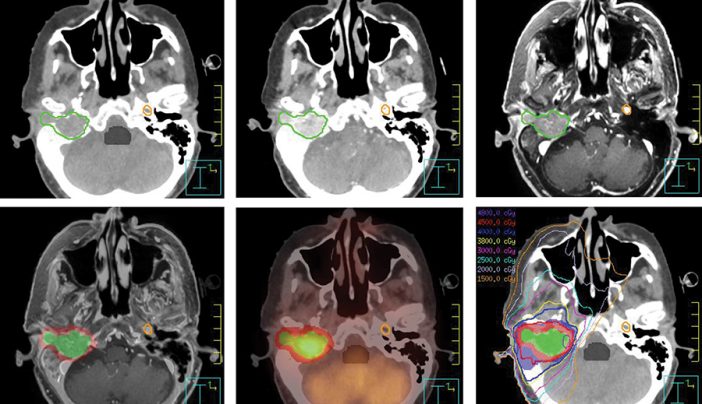

Gamma knife stereotactic radiosurgery srs especially when used as an adjunct to other therapies offers a better chance of longer survival.

Stereotactic radiosurgery brain metastases side effects. Side effects of radiosurgery are usually related to sending high doses of radiation to particular areas of the skull. Side effects of brain tumour treatment side effects of stereotactic radiotherapy stereotactic radiotherapy treatments generally have fewer side effects than conventional radiotherapy as less healthy brain tissue is affected and a lower dose of radiation is used. Side effects of stereotactic radiotherapy and radiosurgery. For instance if you are treated for an acoustic neuroma a tumor involving the nerve that controls hearing you might lose some hearing.

Srsmay also be used to treat cancers that have spread to the brain from other parts of the body brain metastases. It delivers precise highly focal control of brain metastases with few side effects. Stereotactic radiotherapy and radiosurgery isn t suitable for everyone. Stereotactic radiosurgery such as gamma knife is often used to treat noncancerous benign and cancerous malignant brain tumors including meningioma paraganglioma hemangioblastoma and craniopharyngioma.